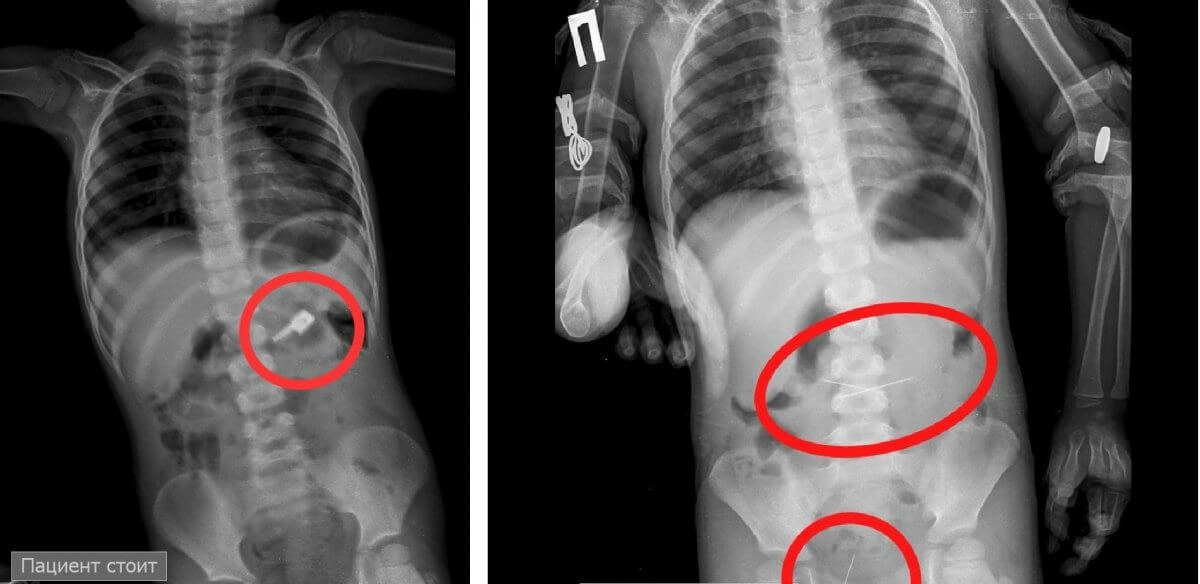

При обзорной рентгенограмме брюшной полости помимо бегунка были обнаружены предположительно две швейные иглы в проекции желудка. При проведении процедуры ЭФГДС из желудка удалили иглу, бегунок отсутствовал.

Пациент был оставлен в хирургическом отделении ЖОМДБ под наблюдением специалистов. В результате бегунок со стулом вышел самостоятельно. В то же время другая игла не отходила. На контрольной R–грамме брюшной полости обнаружены еще две иглы в верхнем этапе брюшной полости и одна игла в проекции таза. Проведена повторная ЭФГДС и удалена игла из желудка. Затем при помощи колоноскопии удалена игла, фиксированная в сигмовидной кишке, – сообщил врач-хирург высшей категории Сейдахмет Байдуллаевич.

Ребенок продолжал находиться под наблюдением. На контрольной R–грамме брюшной полости обнаружили четвертую иглу в проекции таза. Проведена колоноскопия и из сигмовидной кишки удалена последняя игла, которая концом была фиксирована в слизистую кишечника. Сейчас малыш уже дома, с ним все в порядке и он хорошо себя чувствует.